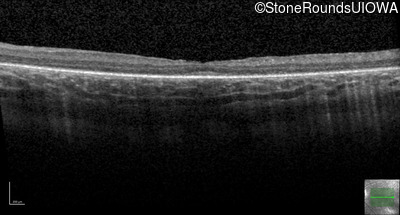

Optical Coherence Tomography - Right - 20/80 -1

Exemplar / OCT Stack

OCT Stack